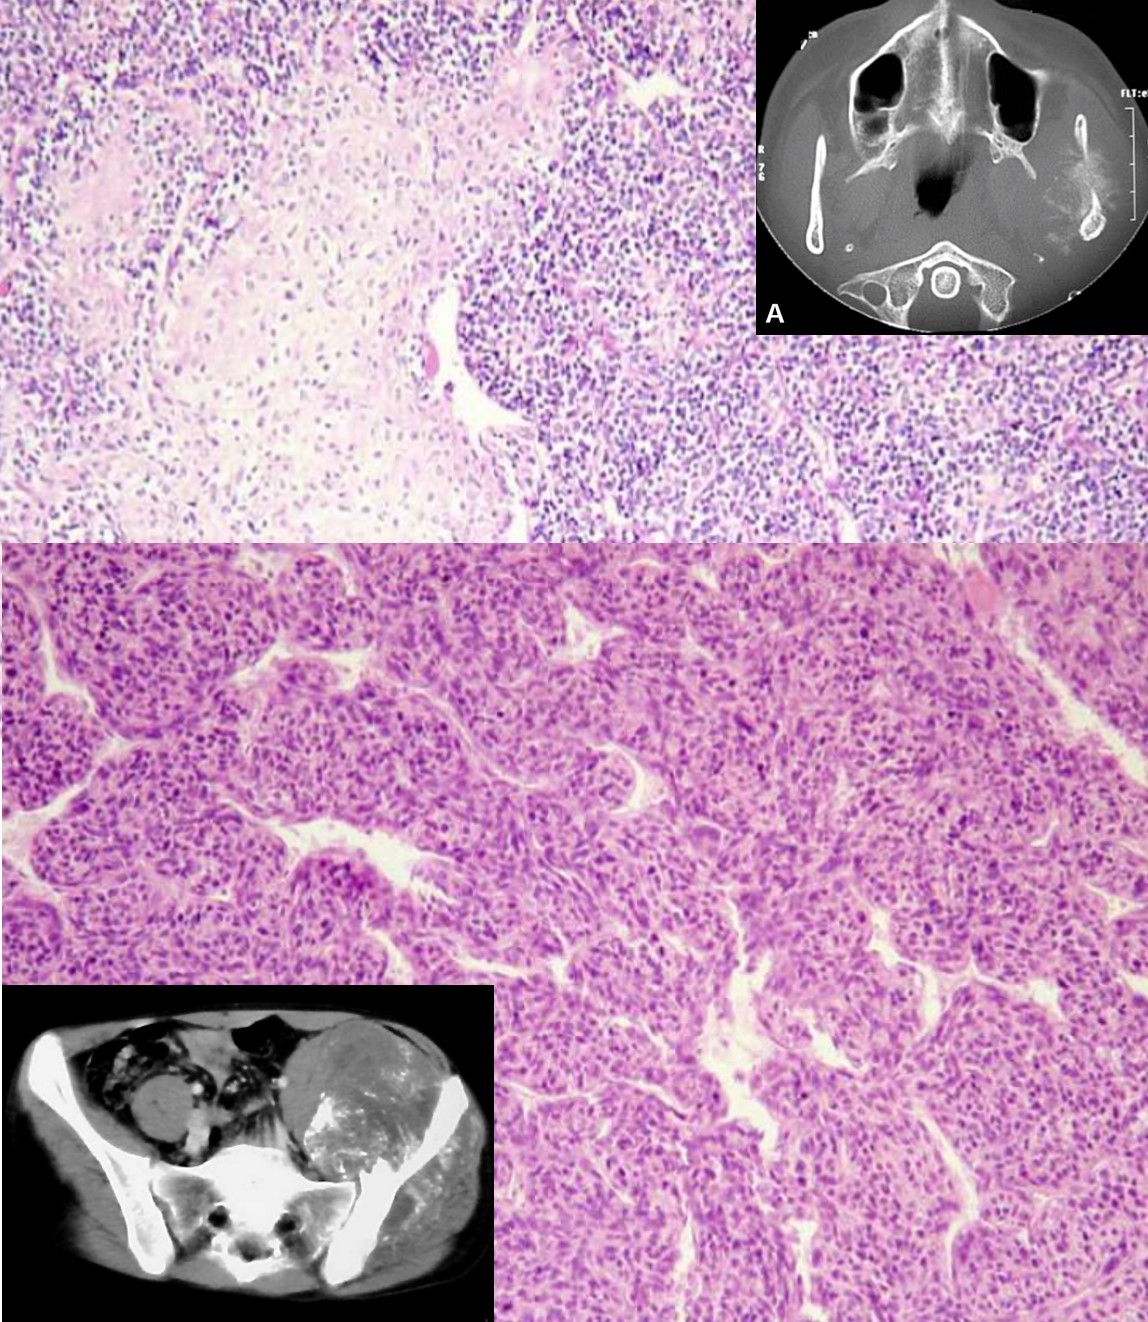

MESENCHYMAL CHONDROSARCOMA

SMALL CELL OSTEOSARCOMA

IDH2/IDH2 mutations